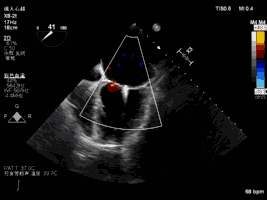

夹合术后:彩色多普勒示轻微二尖瓣反流